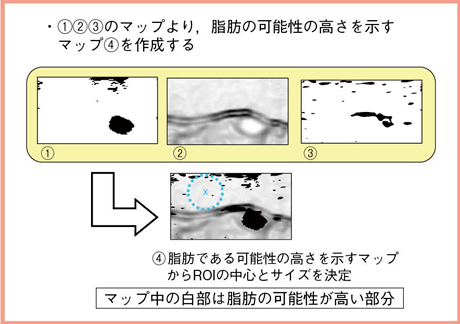

一方,脂肪では3段階のステップでROIを決定する。脂肪そのものを見つけることは難しいため,脂肪の可能性が低い部分を除外するという考え方に基づく。

まず,Bモード画像の輝度から脂肪の可能性が低いマップを作成する。エコーレベルが低い部分は腫瘤の可能性が高く,つまりは脂肪の可能性が低い(図5(1))。また,輝度変化が大きい,何かの境界にあたる部分が脂肪の中心である可能性は低いと言える(図5(2))。

さらに,エラストグラフィ画像から脂肪の可能性が低いマップを作成する。エラストグラフィでひずみの少ない部分は硬いことから,脂肪の可能性は低いと言える(図5(3))。

そして,これらのマップを合わせ,脂肪の可能性の高さを示すマップを作成し,そのマップから脂肪のROIの中心とサイズを決定する(図5(4))。

図5 ROI(脂肪)決定のアルゴリズム:脂肪の可能性が高いマップの作成